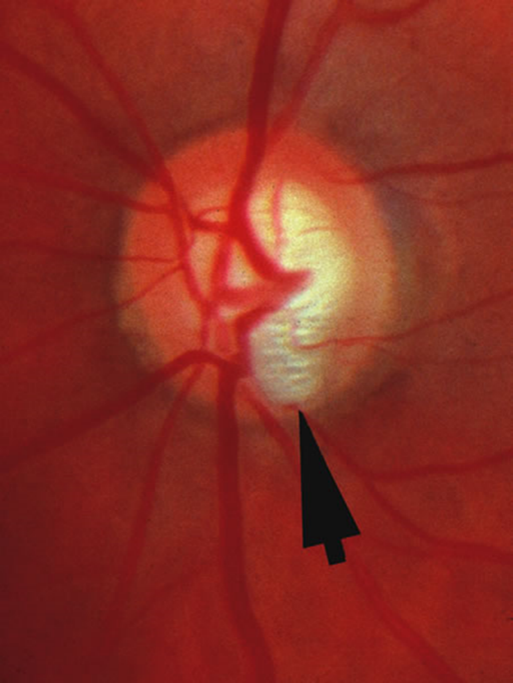

Notch - optic disc

Glaucomatous optic neuropathy

Optic Disc Haemorrhages